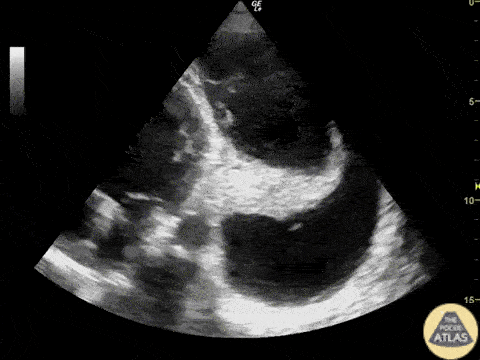

38-year-old woman admitted to the ER with complaint of progressive dyspnea. Apical four chamber view on the FOCUS exam showed atelectasis of left lung from a huge pleural effusion next to the heart. Image courtesy of: Dr. Renato Tambelli, Emergency Department of Marilia Clinic Hospital, São Paulo, Brazil / POCUSJEDI Team @JediPocus